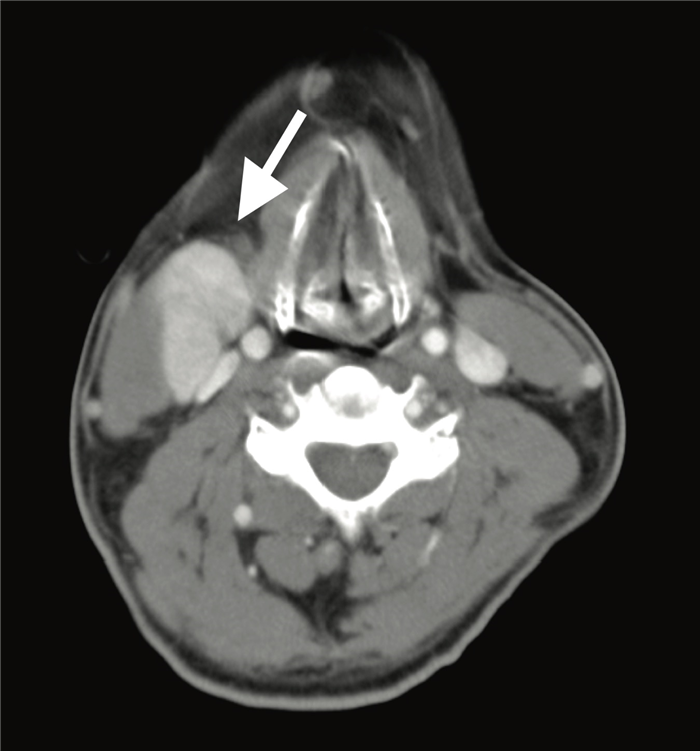

На постконтрастном изображении белой стрелкой указан увеличенный лимфатический узел VI группы.